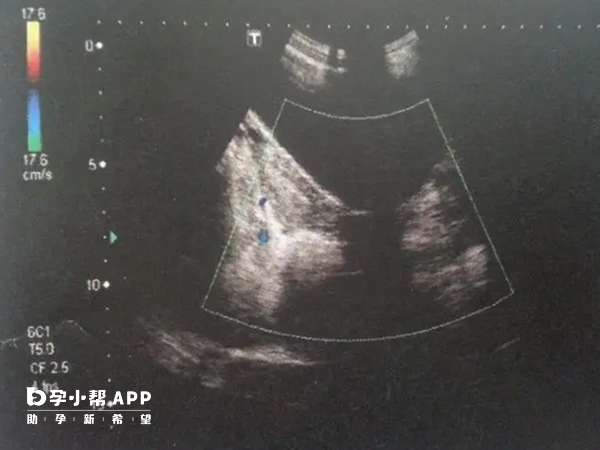

- 1. 经阴道超声、三维超声成像、宫腹腔镜等等都是子宫畸形检查方法中常用的手段,而其中三维超声检查不全纵隔子宫双侧内膜夹角较锐利,为64-90°,弓形子宫内膜夹角钝圆,为103-152°;

- 2. 不全纵隔子宫的子宫底内膜宫腔镜检查见宫底略内突,两侧宫角深,深度超过10mm,腹腔镜见宫底轮廓正常或有凹陷,宫底部内膜凹陷深度小于10mm,则为鞍状子宫(弓形子宫)。